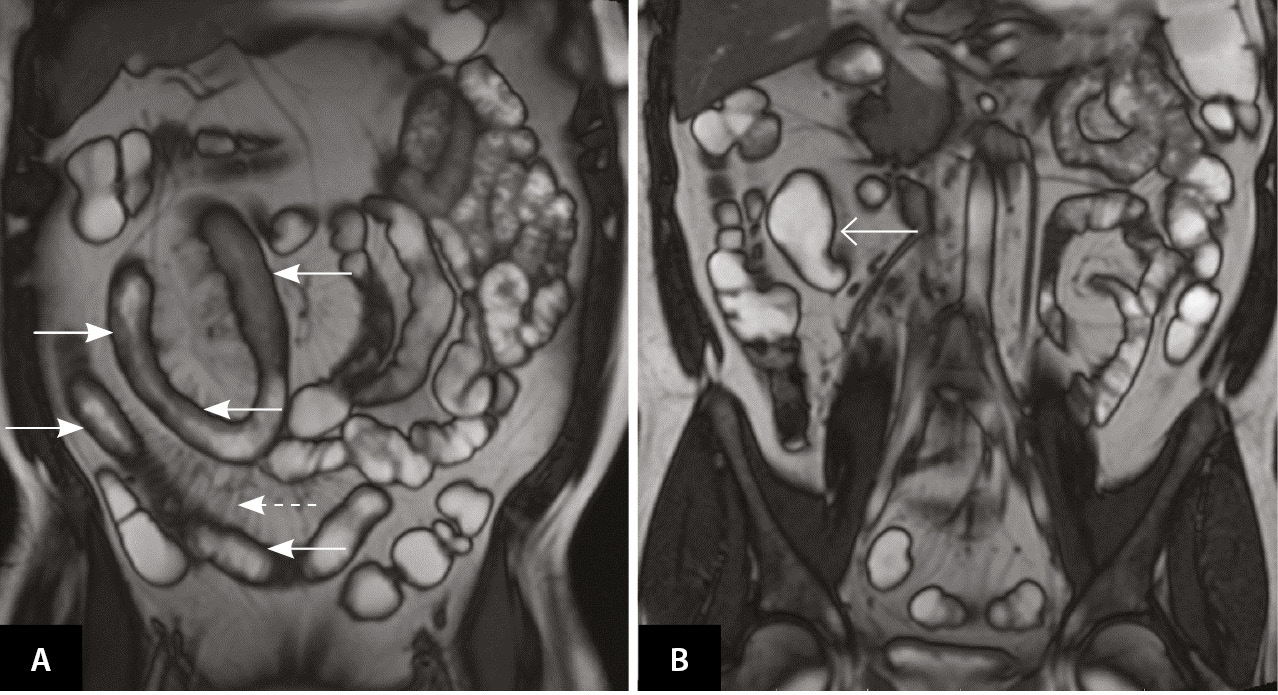

Осенью 2019 г. (в возрасте 39 лет) пациент обратился в кабинет воспалительных заболеваний кишечника (ВЗК) ФГБОУ ВО «Первый Санкт-Петербургский государственный медицинский университет имени академика им. И. П. Павлова» Минздрава России. При лабораторном обследовании выявлено повышение скорости оседания эритроцитов до 62 мм/ч (норма (N) – 2–15 мм/ч), С-реактивного белка (СРБ) до 63,01 мг/л (N ≤ 5 мг/л), фекального кальпротектина (ФК) до 1039 мкг/г (N ≤ 50 мкг/г). Результат ЭГДС: по большой кривизне тела желудка язвенный дефект 0,7 × 0,5 см, дно язвы под фибрином с налетом гематина, край умеренно приподнятый. Гистологическое исследование биоптата слизистой оболочки желудка: эпителизирующаяся острая эрозия фундального отдела желудка, хронический фундальный гастрит со слабым воспалительным компонентом, минимальной активностью, обсеменения Helicobacter pylori не выявлено. При ИКС наблюдалось сужение подвздошной кишки (на 5 см дистальнее баугиниевой заслонки), непроходимое для эндоскопа диаметром 12 мм, отек и гиперемия слизистой оболочки терминального отдела подвздошной кишки с утолщенными ворсинами и множественными сливными афтозно-язвенными дефектами под фибрином, а также деформация илеоцекального клапана с формированием на поверхности плоских язвенных дефектов до 1,0–1,5 см (9 баллов по SES-CD (англ. Simple Endoscopic Score for Crohn’s Disease – Простая эндоскопическая шкала БК)). При гистологическом исследовании обнаружен хронический сегментарный эрозивно-язвенный илеит с фокально выраженным воспалительным компонентом и высокой активностью, толстокишечной метаплазией эпителия; хронический сегментарный эрозивно-язвенный баугинит с фокально выраженным воспалительным компонентом и высокой активностью, распространенной воспалительной инфильтрацией в подслизистом слое, без признаков гранулематозного компонента; поверхностный колит с минимальным воспалительным компонентом, без активности. По данным магнитно-резонансной энтерографии выявлены признаки стриктурирующей формы БК умеренной активности (по классификации J. Panes) с поражением дистальных петель и терминального отдела подвздошной кишки (рис. 1).

Рис. 1. Магнитно-резонансная энтерография (01.10.2019), Т1-взвешенное изображение после внутривенного контрастного усиления (гадобутрол, 5 мл), фронтальная проекция: A – асимметричное утолщение стенки в дистальных петлях подвздошной кишки и терминальном отделе подвздошной кишки (сплошные стрелки), незначительно выраженная сосудистая реакция брыжейки (пунктирная стрелка); Б – престенотическое расширение подвздошной кишки перед местом поражения (открытая стрелка)